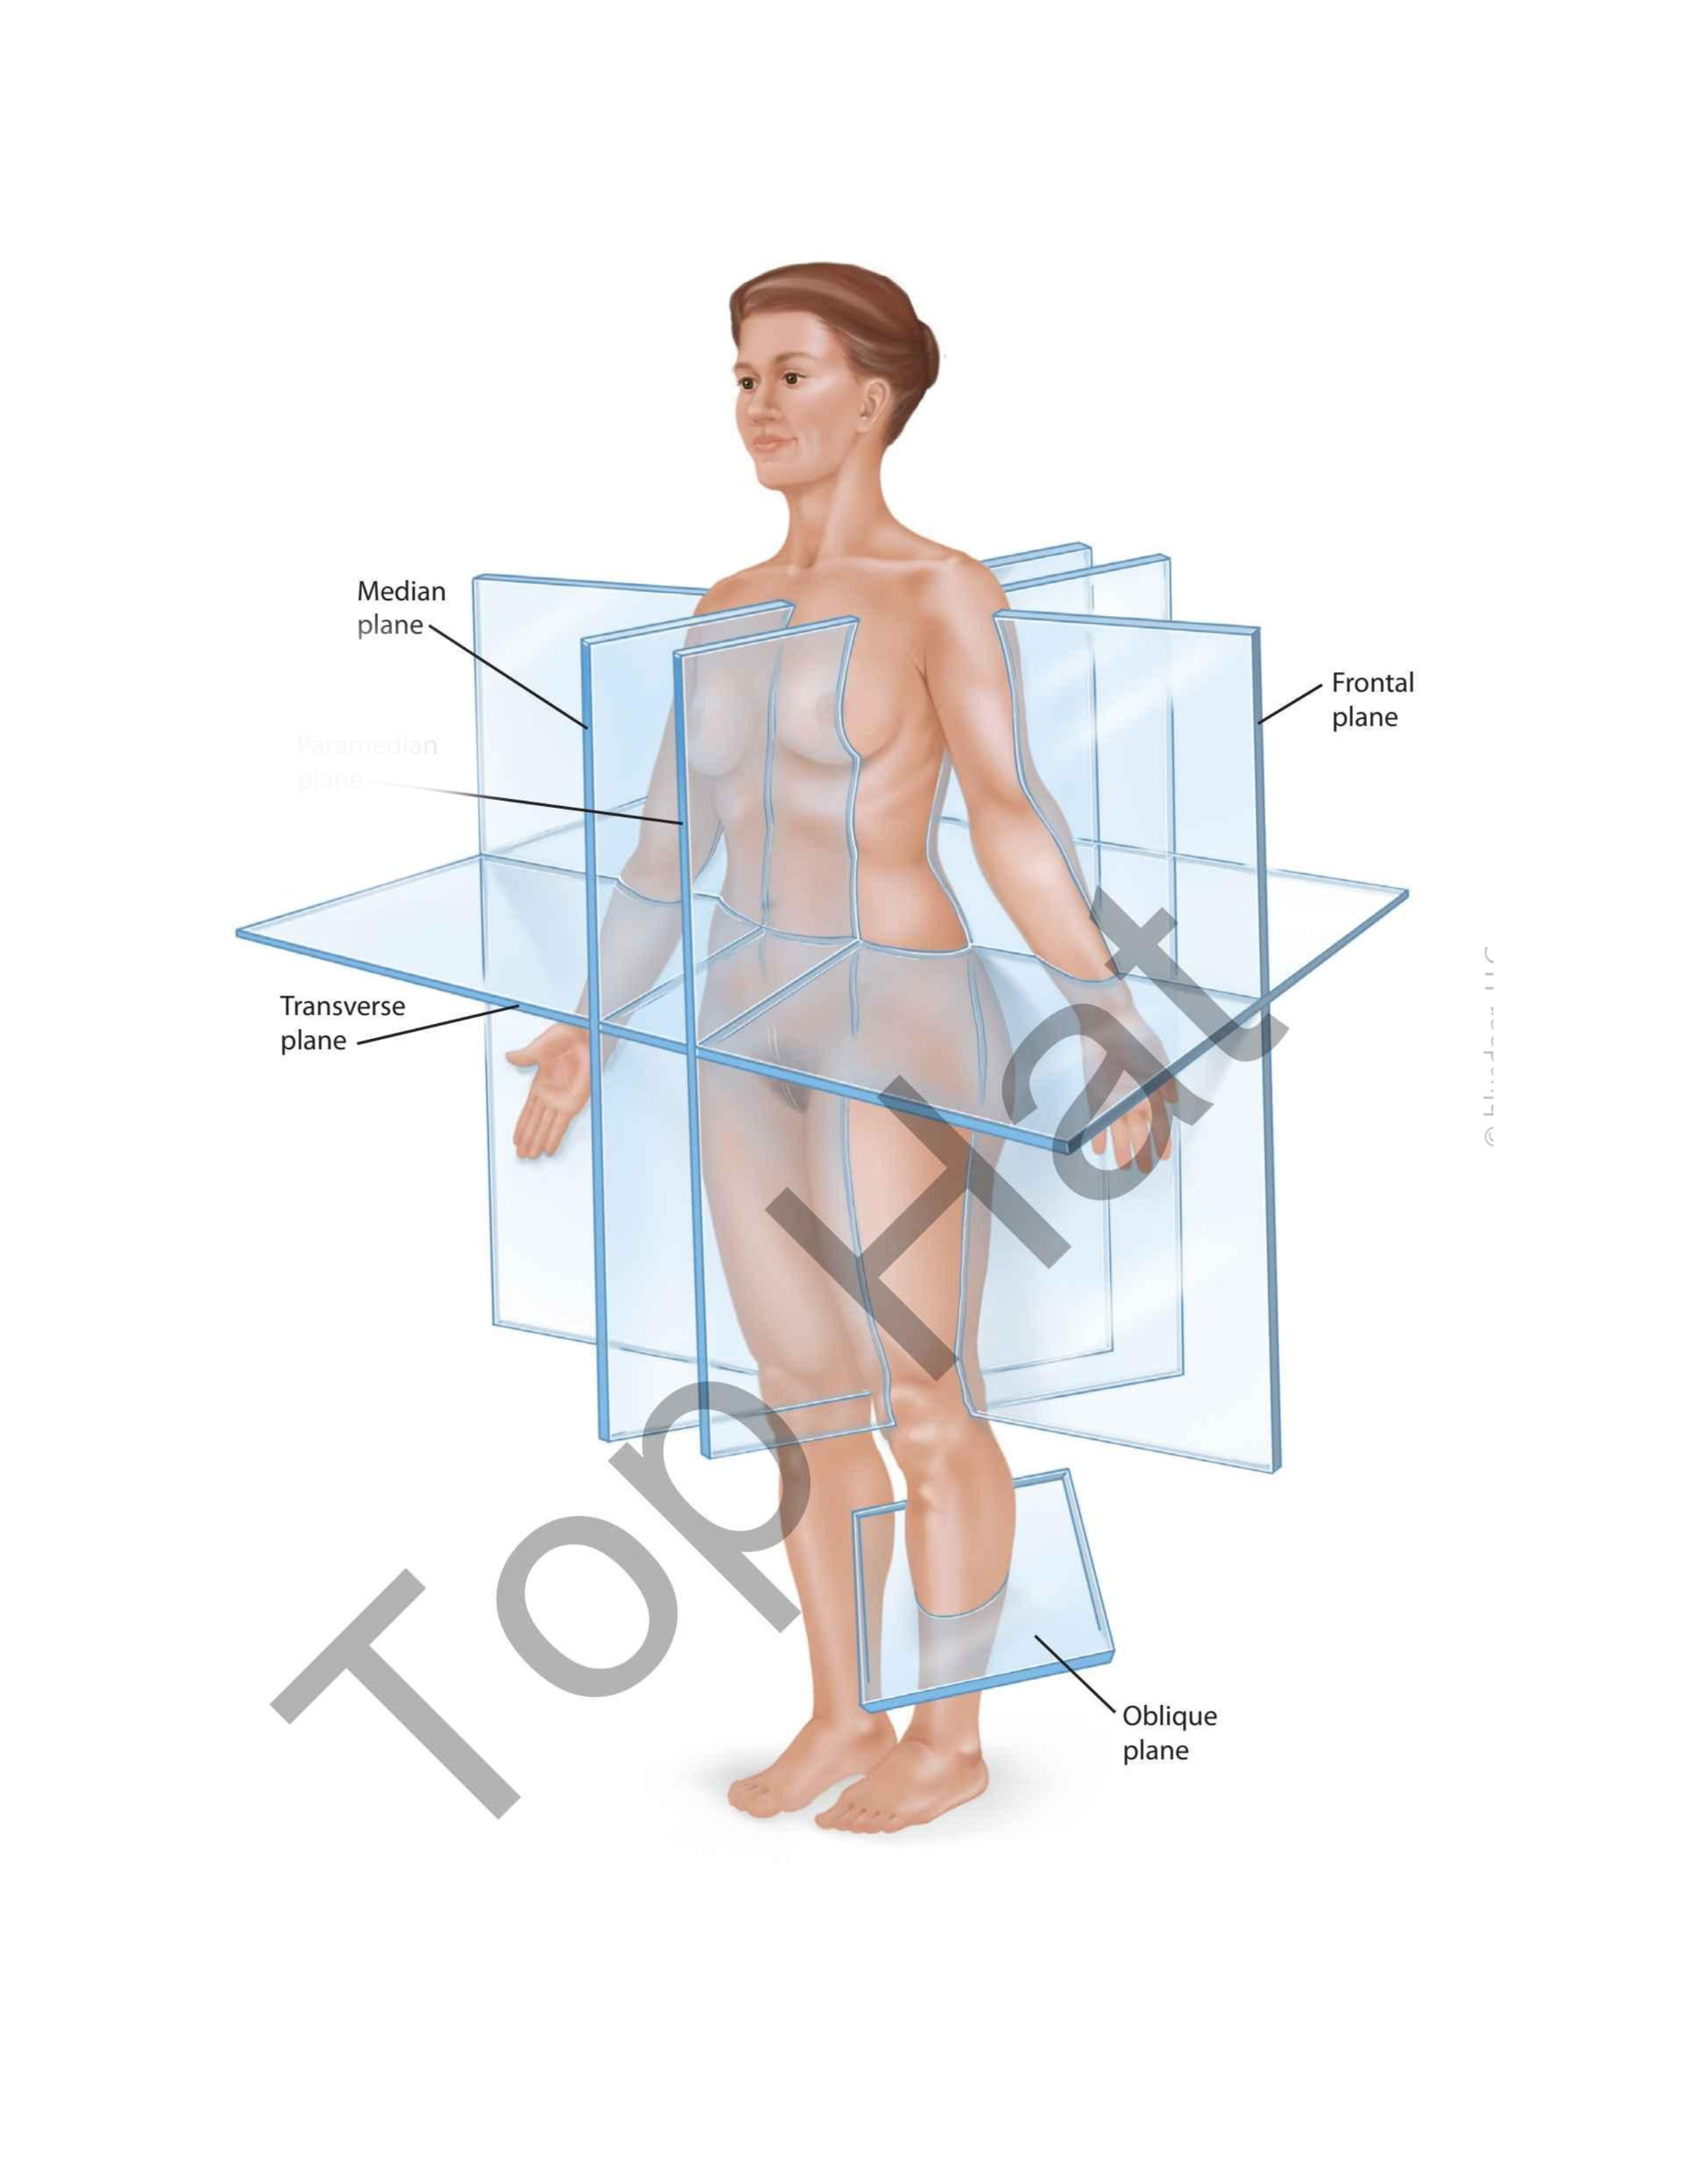

Median Plane

Frontal Plane

Oblique Plane

Transverse Plane

Paramedian Plane